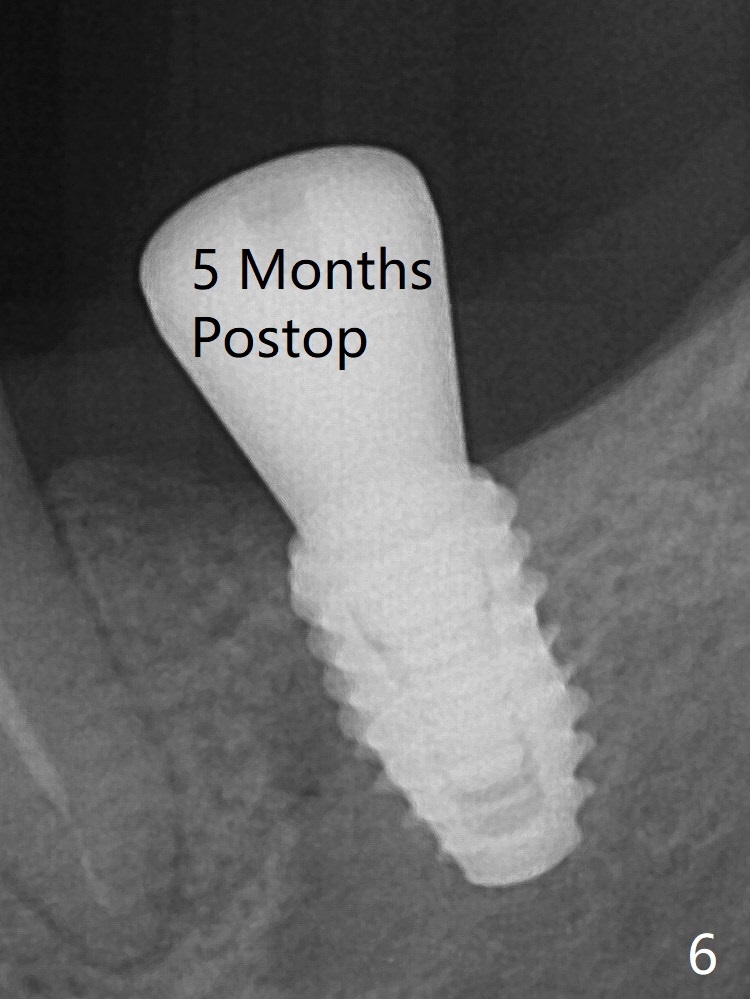

Fig.3: Implant placement at #19 with guide. The gingiva around the healing abutment (5.5x3 mm) at #19 is erythematous (Fig.5), probably related to the submerged abutment. There is no bone loss 5 months postop (Fig.6).